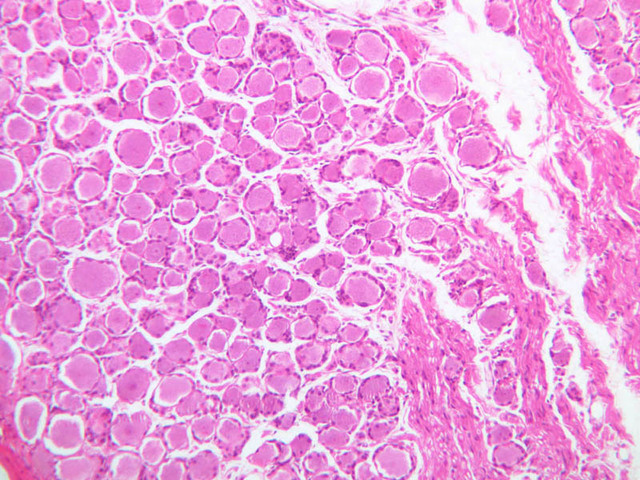

The CNS is a densely packed tissue comprised of neurons and their processes as well as a number of non-neuronal, or neuroglial cells. Neurons and their processes are surrounded and ensheathed by various types of glia. In contrast to the PNS, there is no vascular connective tissue stroma surrounding neurons in the CNS. The glia in the CNS can be divided into the macroglia, which consist of the astrocytes and oligodendrocytes, and the microglia, which are macrophage-like cells. Among the macroglia, oligodendrocytes are most prevalent in the white matter where they function like Schwann cells to produce and maintain CNS myelin. Unlike Schwann cells, which myelinate a single internode, an oligodendrocyte may myelinate up to 30 individual myelin internodes.

In slide A-82 of spinal cord, find the white matter (A-82, H&E [10x, 20x, 40x] [20x, 40x-labeled]), which surrounds the gray matter ([2.5x, 10x, 20x, 40x]). Does its appearance remind you of a peripheral nerve in cross section? The white matter is comprised of axons that originate from neuronal cell bodies lying in the gray matter of either spinal cord, brain, or spinal ganglia. Axons in the white matter can be thought of as parallel cables that ascend or descend the length of the spinal cord. The white matter does not contain any neuronal cell bodies, thus the nuclei present in this area are those of oligodendroglia, fibrous astrocytes, microglia, or endothelial cells. These cells become readily distinguishable with immunohistochemistry.

On slide A-88 (H&E of spinal cord cut longitudinally [2.5x, 10x, 20x, 40x-labeled] [10x, 20x, 40x-labeled]) look in the white matter at the edges of the section for small cells with darkly stained, round nuclei. These will be oligodendrocytes. In particular look for rows of adjacent oligodendrocytes. Also situated among the nerve fibers in the white matter are fibrous astrocytes. These are easier to find in the white matter of the spinal cord in cross section (slide A-82). Astrocytes have star-like morphologies and often the process of one astrocyte will abut the process of an adjacent astrocyte. White matter astrocytes also have a larger nucleus than the oligodendrocytes, and astrocytic nuclei are oval in contrast to the spherical nuclei of oligodendrocytes. Also, examine the caramates for examples of immunohistochemically stained oligodendrocytes, astrocytes and microglia. Without special stains it is almost impossible to positively identify microglia. These cells will have dark, thin, elongated nuclei. They are readily apparent using immunohistochemistry with antibodies that label monocytic lineage cells or with specific lectins.

Closely observe the cross section of the spinal cord in slide A-82. The central grey matter contains numerous large neurons and the eosinophilic ground substance is the neuropil. Many of the nuclei between the large neurons are neuroglial cells. Because of their gray matter location these would be either oligodendrocytes or protoplasmic astrocytes. The astrocytes within the grey matter are difficult to positively identify without immunohistochemistry.